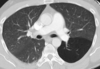

Enfisema

TC en enfisema

* Diagnóstica * Distingue distribución (centrolobulillar, panlobulillar o paraseptal) * Engrosamiento bronquial * Atrapamiento aire

EPOC centrolobulillar

EPOC panlobulillar

EPOC paraseptal